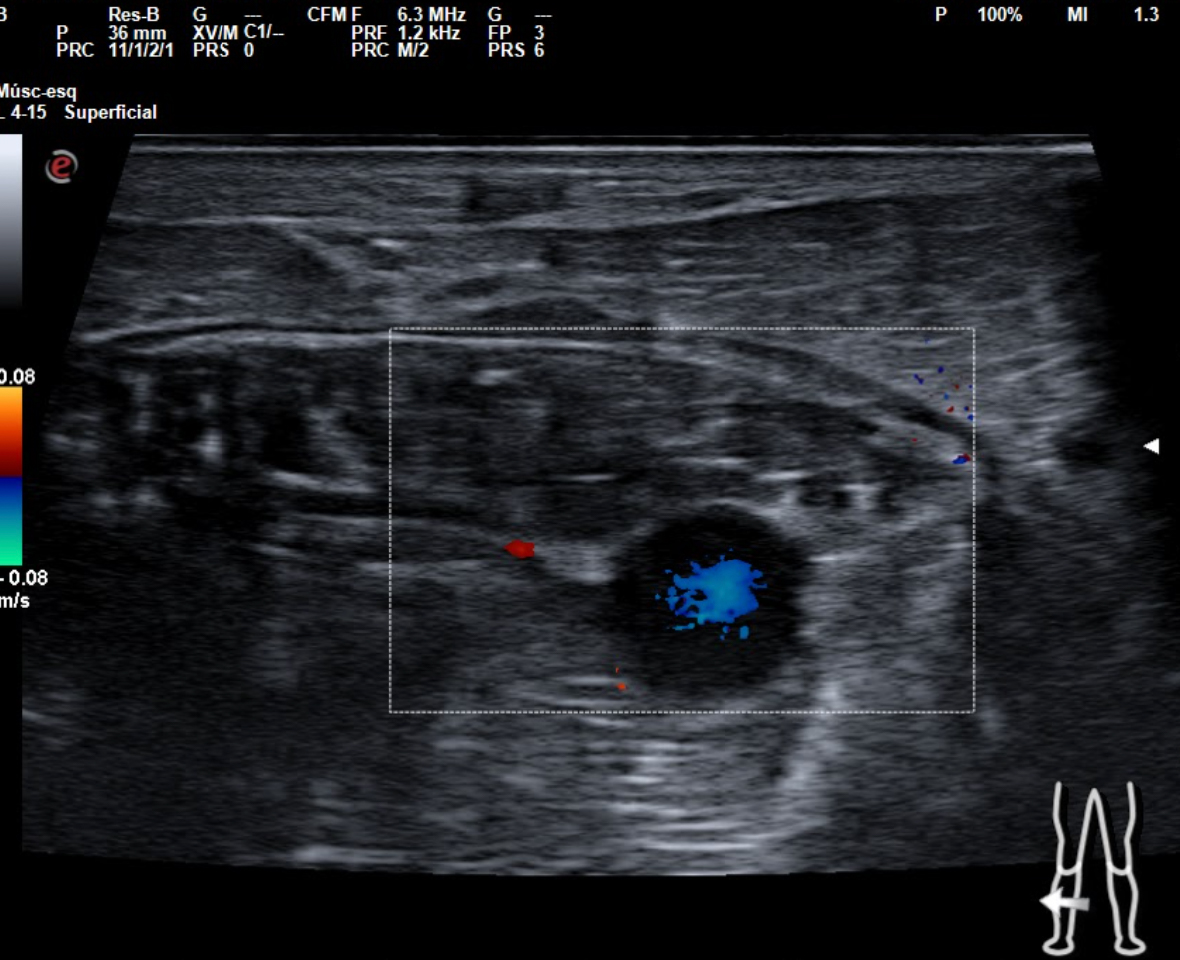

Hallazgos ecográficos

En tendón aquíleo izquierdo se aprecia rotura completa con solución de continuidad de 2 cm localizada a 5,7 cm de su inserción en el calcáneo. Presenta áreas hipoecoicas peritendón que sugieren hematoma secundario. En el aquíleo derecho presenta leve hipoecogenicidad y engrosamiento del tendón sin solución de continuidad que sugiere tendinosis. Importante componente inflamatorio. No datos de TVP. Poplítea y safena externa permeables y compresibles en ambas extremiedades.

Juicio clínico: Rotura completa de tendón de Aquiles izquierdo. Tendinosis aquílea derecha.